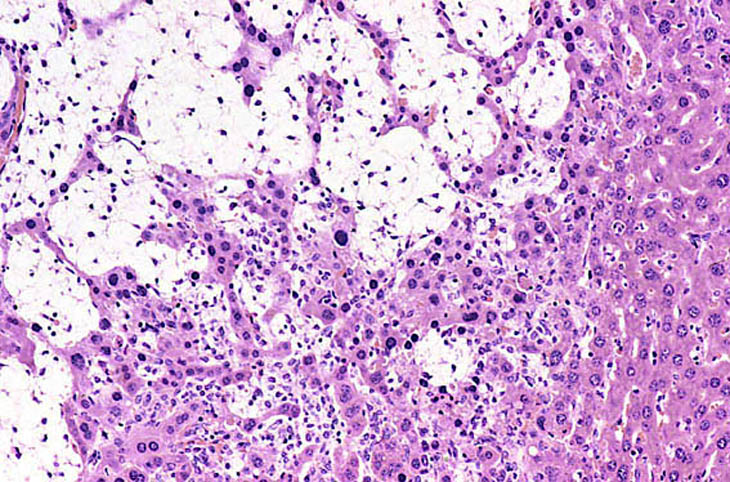

An Ito cell tumor that has replaced much of the normal hepatic parenchyma without distorting the normal contour of the liver; higher magnification shows fat-filled and stellate cells in the hepatic sinusoids.

The proliferating stellate cells have a myxomatous appearance in some areas and have caused atrophy of hepatic cords.